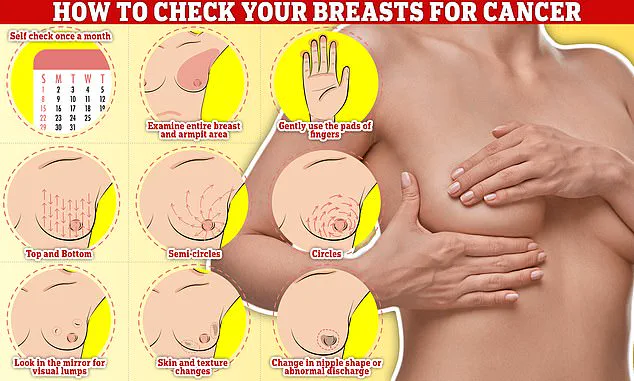

Early detection remains a cornerstone of effective treatment, and self-examination is a critical tool in this effort.

Checking your breasts should be part of your monthly routine so you notice any unusual changes.

Simply rub and feel from top to bottom, feel in semi-circles, and in a circular motion around your breast tissue to feel for any abnormalities.

Women are encouraged to check their breasts regularly for potential signs of the cancer.